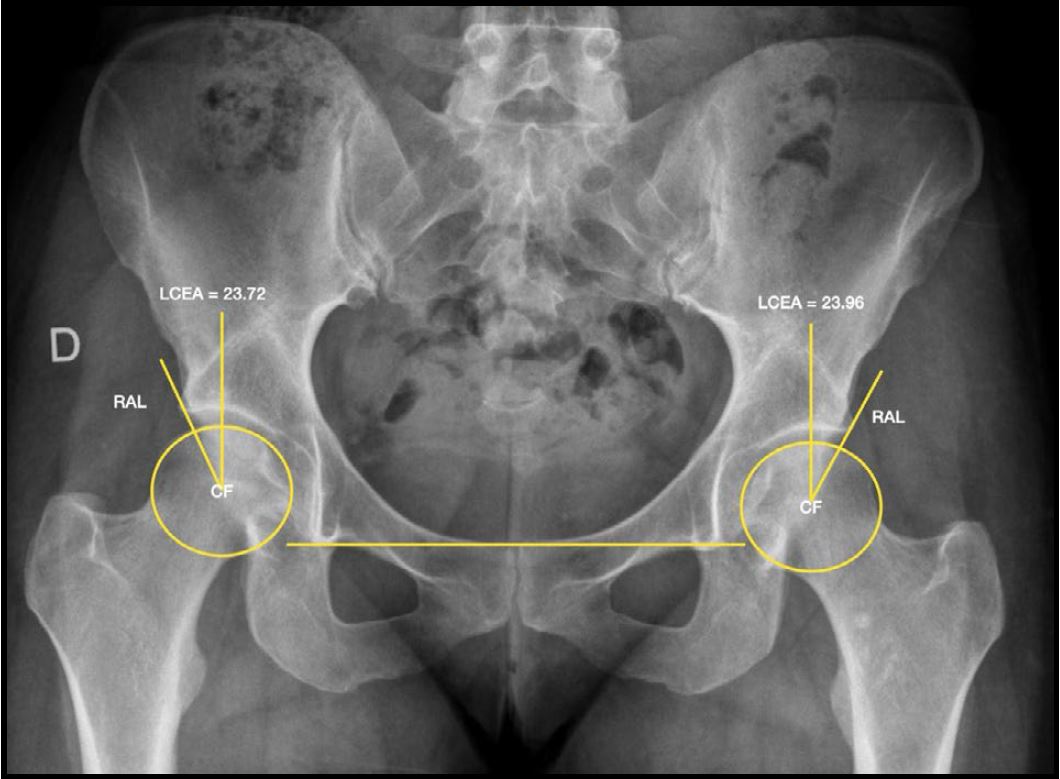

La evaluación por imágenes incluyó radiografías de pelvis anteroposterior, proyección de Lowenstein y de Dunn, resonancia nuclear magnética (RNM) de al menos 1.5 Tesla con cortes acetabulares radiales, y tomografía computada con reconstrucciones radiales para la evaluación detallada de deformidades femorales y acetabulares mediante mediciones angulares con distribución horaria. El punto de corte para el diagnóstico de displasia limítrofe fue un ángulo centro-borde lateral (LCEA de Wiberg) entre 20° y 25° (Fig. 1). La RNM fue utilizada para la detección de patología labral y/o condral asociada (Fig. 2). Las características demográficas y clínicas de la muestra se detallan en la Tabla 1.

Figura 1. Radiografía A-P de pelvis que muestra la medición del ángulo centro-borde lateral (LCEA de Wiberg) en ambas caderas. Se señalan el centro de la cabeza femoral (CF) y el reborde acetabular lateral (RAL) como referencias anatómicas para la medición del ángulo de cobertura acetabular.